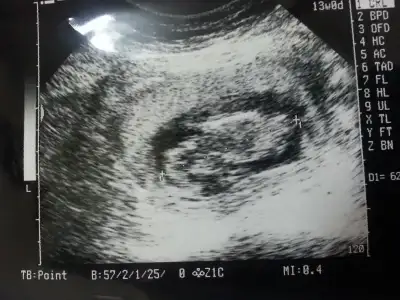

dr soylemeden siz gorun genital nub teorisi ( bebegin cinsiyeti)

$20140624_005921.webp $20140624_005759.webp kızlar bi bakın hele fananay orkide yorum bekliyorum sizdende diğer kızlardanda nolurrrrr:52:

Canım bu benim.oğlumun 12 haftalıkkenki ultrasonu